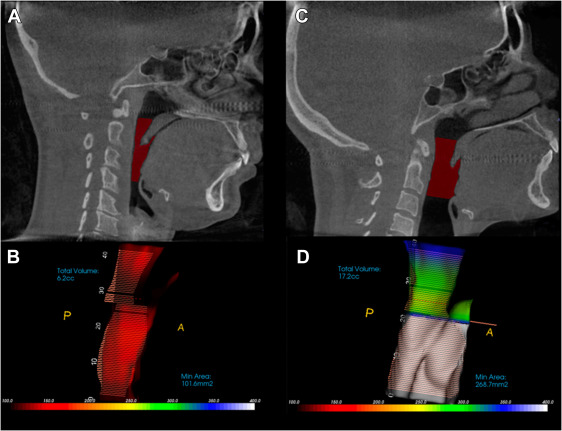

左圖:正常頭頸姿勢下狹窄的呼吸道。右圖:變成烏龜頸姿勢後呼吸道變寬 (https://doi.org/10.1016/j.joms.2023.01.016)